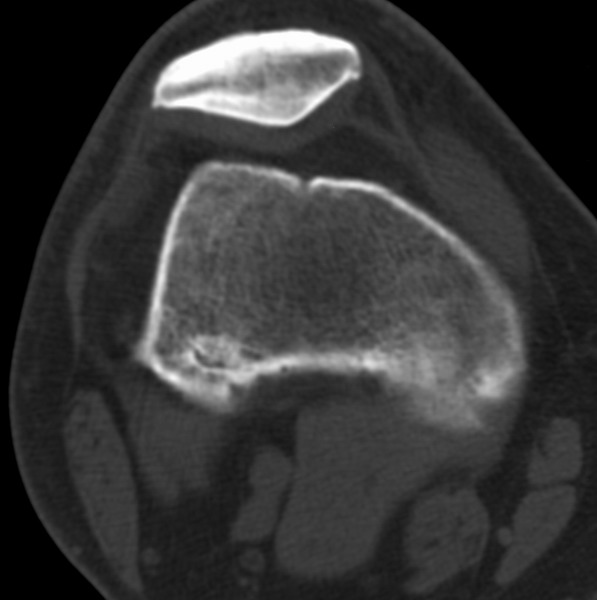

标题: CT21959:骨肿瘤请会诊。

右侧膝关节疼痛一月

男、48

股骨下段、胫骨上段。

1、股骨干骺端病变考虑干骺端纤维性皮质缺损愈后(非骨化性纤维瘤)改变,胫骨近端内生骨瘤(或干骺端纤维性皮质缺损愈后改变);

2、骨关节炎,骨质增生,股骨外侧髁退变性囊肿(关节面软骨下囊肿);

3、髌骨前缘裂纹骨折?